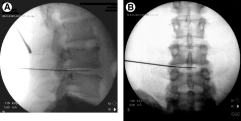

• 2. Imaging Guidance:

• Fluoroscopy or other imaging techniques are used to guide the procedure.

• This ensures precise placement of the instruments and targeted treatment of the affected disc.

• 3. Needle Placement:

• A thin needle is inserted through the skin and guided towards the affected disc under fluoroscopic guidance.

• The needle is carefully positioned to reach the center of the disc where the problem lies.